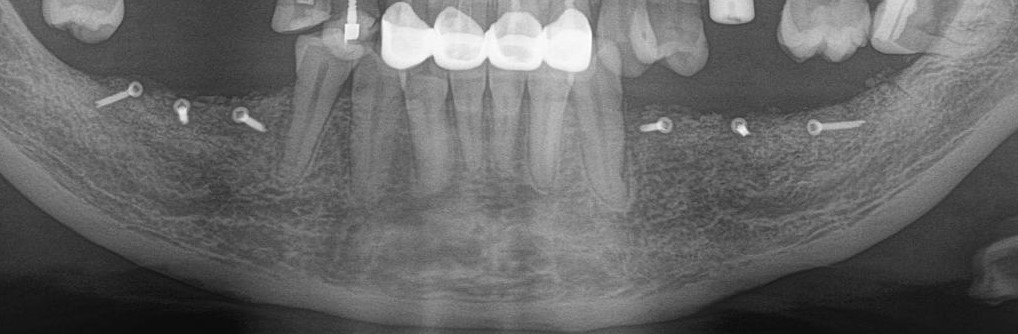

Рентгеновский снимок после имплантации:

И спустя 3.5 месяца на этапе временных коронок (коронок не видно потому, что материал, из которого они изготавливаются, не рентгеноконтрастен):

Дружок в лице горизонтального зуба мудрости (на снимке справа) успешно был удалён.